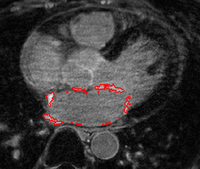

Scar Tissue Identification for Post-Ablation AnalysisThe delay-enhanced MRI (DE-MRI) technique provides an effective way of imaging scarring and fibrosis tissue of atria. Segmentation of the LA from DE-MRI images can be used in atrial fibrillation (AF) treatment to select suitable candidates for ablation therapy and subsequent monitoring of the therapy. More... New: Y. Gao, L. Zhu, A. Yezzi, S. Bouix , A. Tannenbaum. Scar Segmentation in DE-MRI, IEEE International Symposium on Biomedical Imaging (ISBI) , 2012. | |